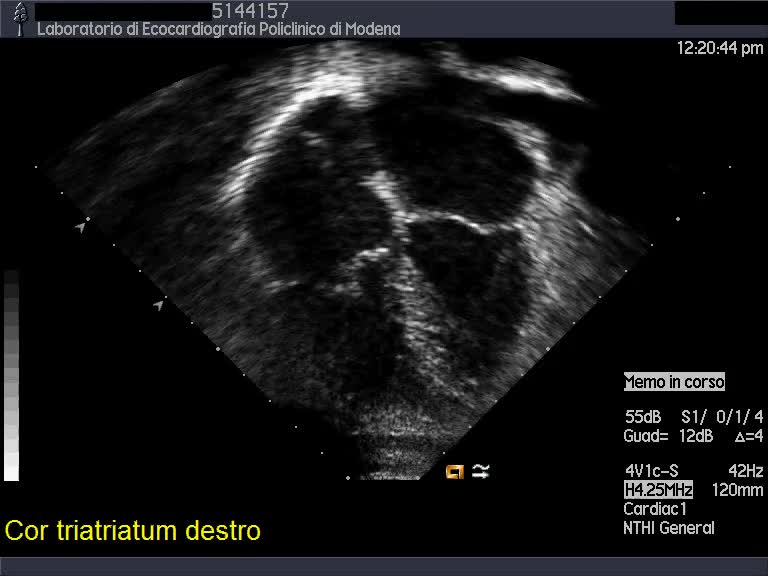

Cor triatriatum dx

Autore:

Andrea Barbieri